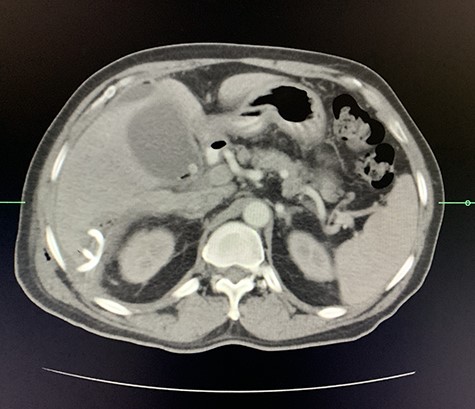

A computed tomography (CT) scan of the abdomen revealed an enlarged, thickened gallbladder with multiple stones, communicating with an intrahepatic collection in segment 4 measuring 116 × 80 mm, with an associated air fluid level and air locules (Fig. 1). There was an apparent fistulous tract to the hepatic flexure of the colon, another large collection in segment 6 (97 × 96 mm) as well as other smaller collections (Figs 2 and 3).

Axial view of portovenous phase of CT scan of the abdomen demonstrating enlarged, thickened gallbladder with radio-opaque gallstones with apparent fistulous communication with the hepatic flexure of the colon with associated pneumobilia.